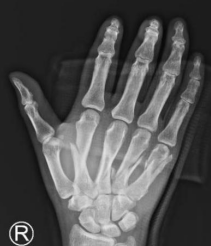

熊医生位患者安排CT检查,见2-5掌骨骨折。“医生,严重吗?”,“你这个属于多发性掌骨骨折,手法复位后,小夹板固定一般达不到满意效果。可以选择切开复位,用克氏针或者钢板内固定。钢板比克氏针固定的更加牢靠,而且不容易为内固定物松动断裂。内固定的优点很多,第一,没有钉道感染的风险;第二,内固定更牢固,不容易移位;第三,术后日常生活很方便,可以在早期进行手部功能的锻炼。”熊医生耐心地为患者解答疑问。

术前